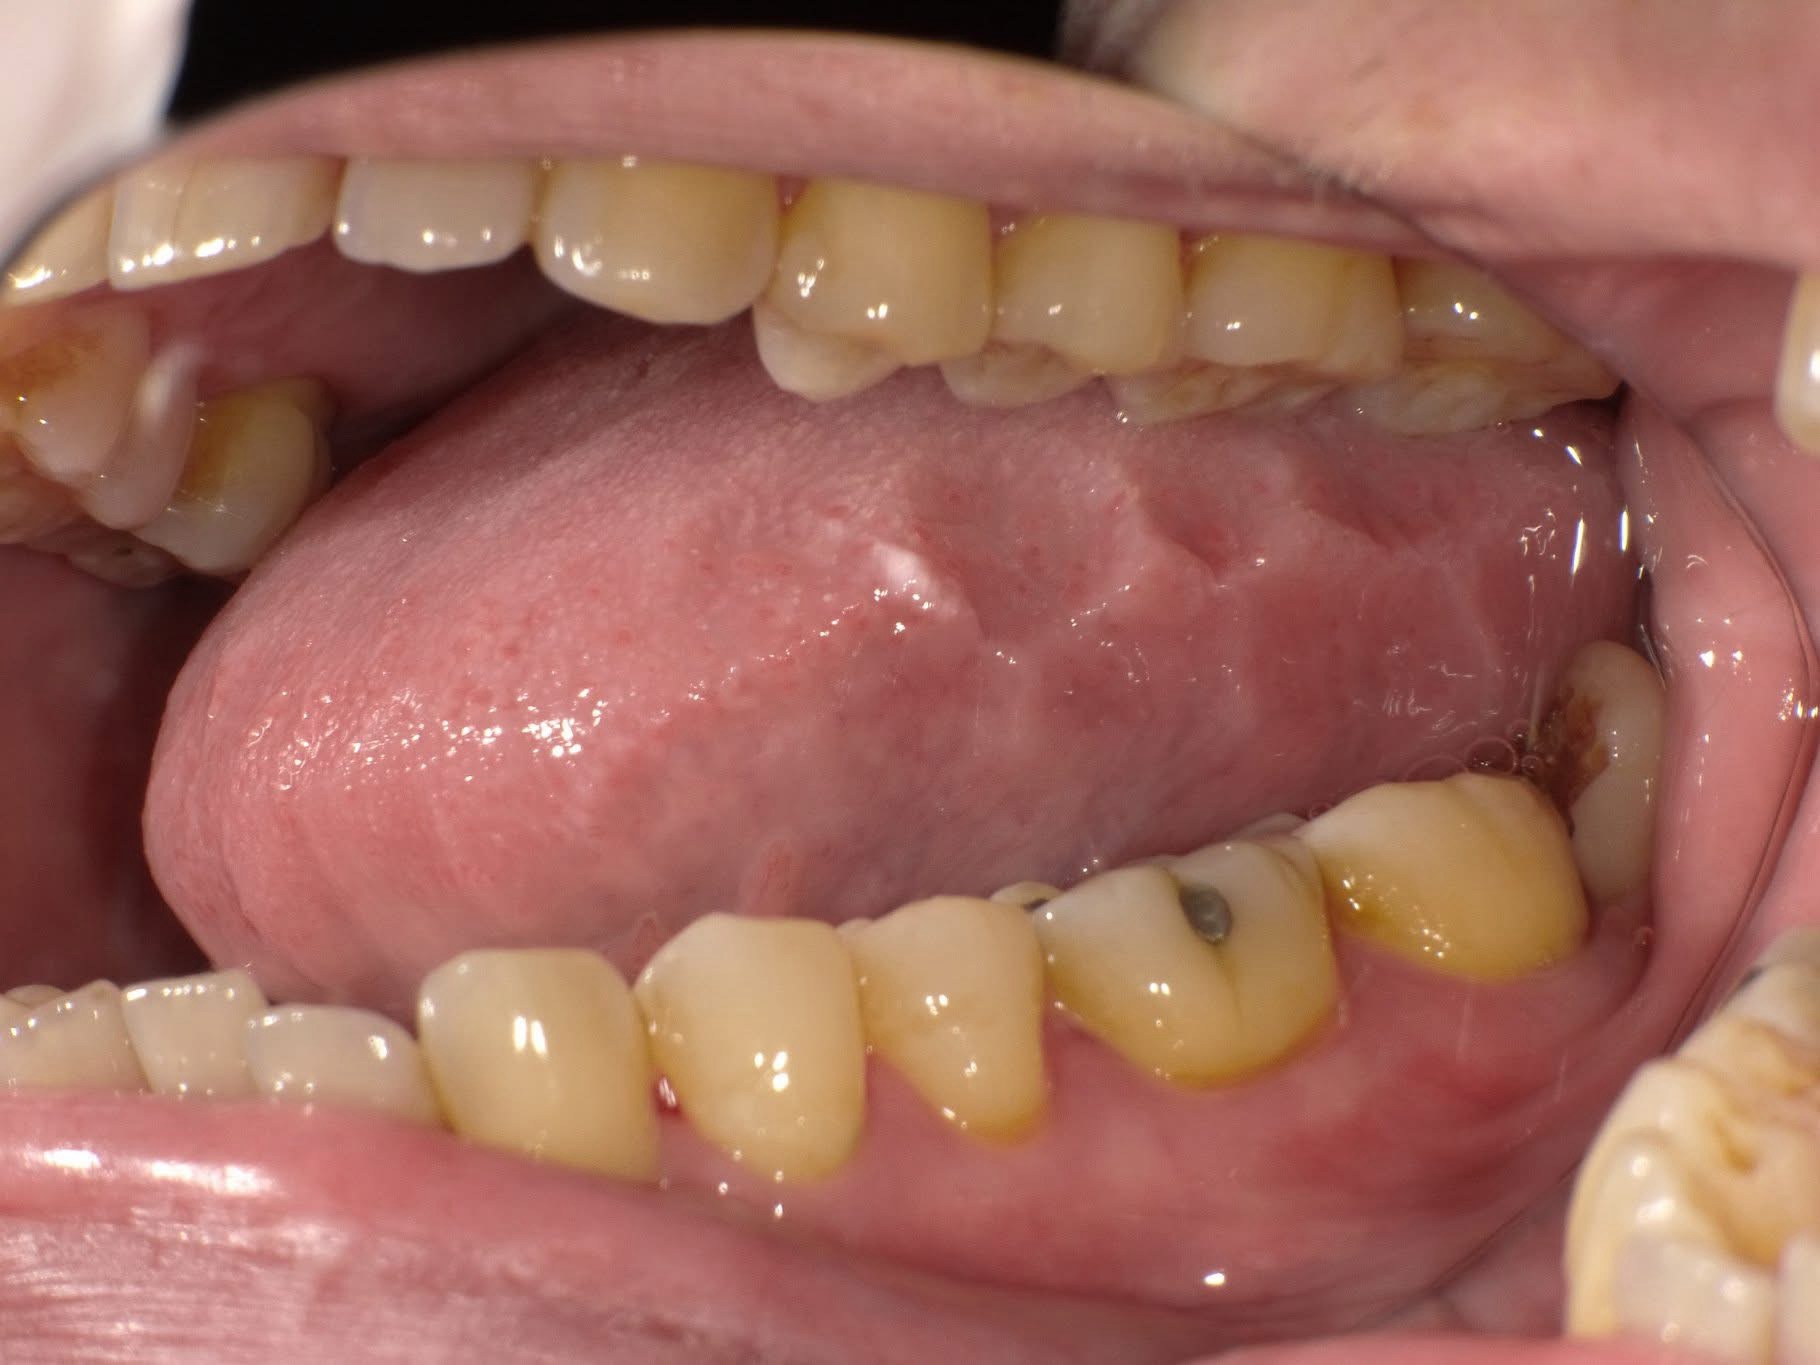

鏡でチェック!舌の横がボコボコしていませんか?「寝たきり舌」を治して若返る方法